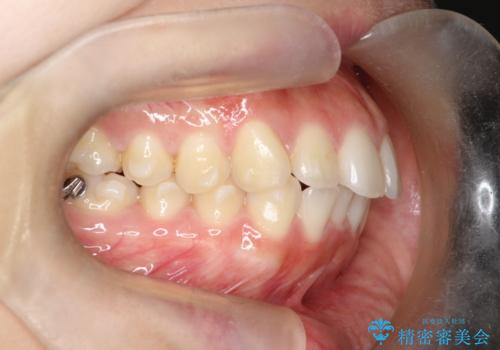

【インビザライン】前歯を下げたい

- 前歯が出ていることを主訴に来院されました。

奥歯を後ろに動かしながらスペースを作ることで、前歯を下げることができ患者さんにも満足していただきました。

治療中に顎間ゴムを使用していただいたおかげで、スムーズに治療を行うことができました。